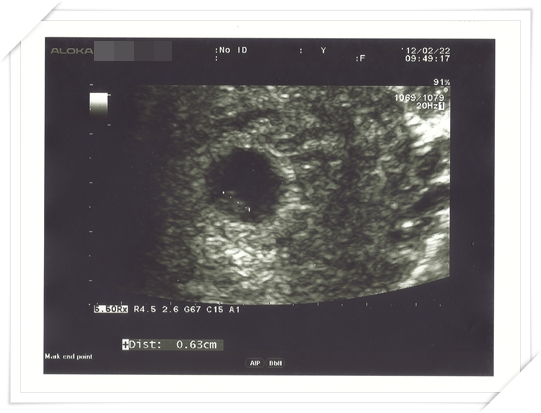

這次醫生很厲害的 居然就照到baby 的心跳啦!

一般來說 如果用腹部超音波 大約都是在八週左右可以看的到心跳

如果是用另外一種 “入侵式” 的超音波 (恩 懷孕的人應該知道我在講甚麼啦!)

則是在約六週的時候就可以照的到囉!

但是這天回診 醫生先問過我有沒有特別哪裡不舒服後

就請我到後面照超音波

一開始 她來來回回照了一下

後來鎖定了一個地方 就請我忍耐一下

接著就 非常用力!!!!地往下壓 哈哈哈 (還好我那天沒有很想上廁所 不然真的很痛苦)

接著就一直把畫面zoom in zoom in

然後就用游標指出畫面上一直顫抖的地方

告訴我 這就是baby 的心跳啦!!!!!!

那時我的反應很好笑 還問醫生說“所以五六週就可以照的到心跳嗎?”

然後醫生的反應更絕啦!

她回答我說 “可能因為你很瘦吧 沒甚麼阻礙物 所以一下就照到啦!”

不過看到Baby 的心跳我總算安心啦

因為代表不是子宮外孕囉!

而且 也表示Baby 長得很好 已經有心跳啦 是個”人” 啦!!